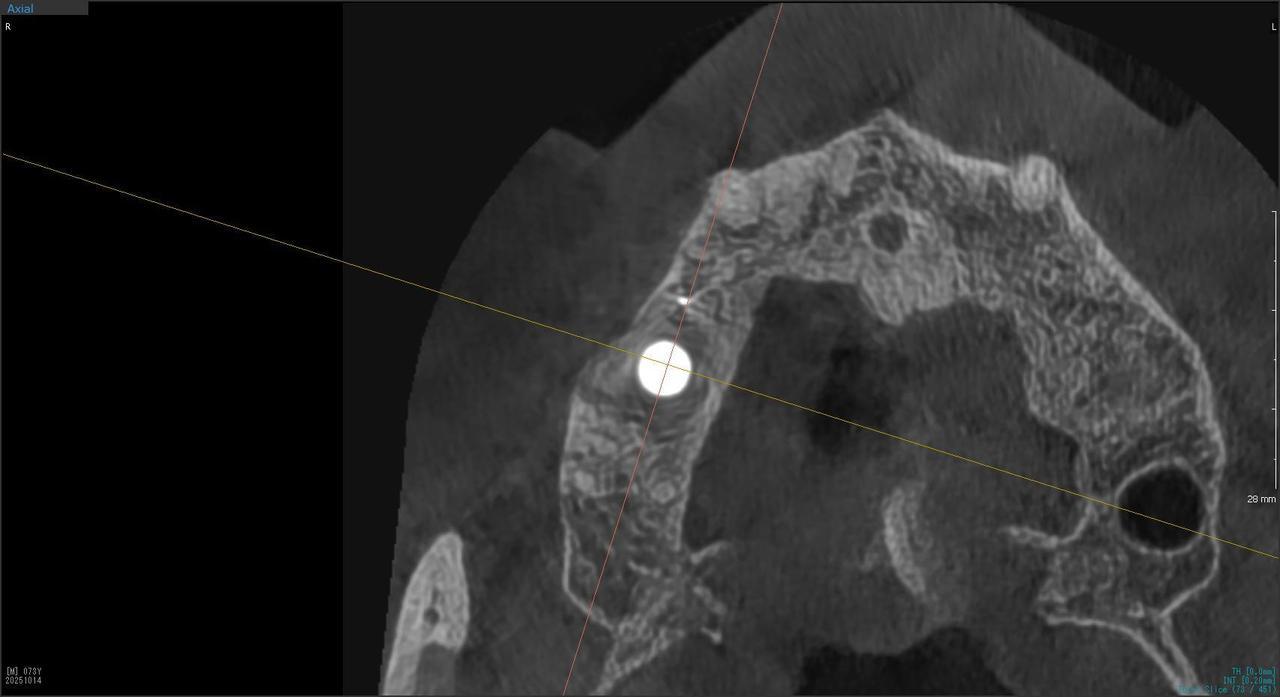

5.左上4番のインプラント抜歯即時埋入、左上6番の上顎既存骨1から2mmのグラフトレスサイナスリフト、左下56の大幅な骨欠損により、下顎神経の損傷を回避するために、ショートインプラントを使用し、左下56にインプラントを埋入し、最終補綴物は、左上456の3ユニットのジルコニアブリッジし、左下56は、ジルコニアの連結冠を装着したケース

M・I 様 女性 70代

症状としては、左下56は、歯周病で欠損したと考えられるが、かなりの骨欠損をともなっていた。左上456に関しては、動揺が大きく、炎症が起き、排膿、および、歯性上顎洞炎を起こしていた。

治療法としては、動揺がひどくなってきて、炎症の症状もあったため、左上56の抜歯を希望。インプラント治療をその後、希望したため、左上4に関しては抜歯即時埋入。左上6に関しては、既存骨1から2mmでインプラント治療が厳しい状態であったが、グラフトレスサイナスリフトを行い、治療期間5か月はかかるということを説明して、インプラント埋入をおこないました。その後、2か月半後、大幅に骨が欠損している下顎56に対して、ショートインプラントを使用して、下顎神経の損傷を避けて、インプラント埋入を終えています。その後2か月後に光学印象で印象を行い、上顎刺億456歯、3ユニットのジルコニアブリッジを装着。下顎左側56に関しては、骨欠損が大きいため、歯冠長がだいぶ長くなるため、ジルコニアの連結冠を装着して治療を終えた。

治療結果は、上顎6に関しては、既存骨が少なく、厳しい治療ではありましたが、5か月で治療を終え、患者様の負担を最小限に抑えるができたと考えます。(従来のサイナスリフトでは、このようなケースでは1年以上、1年程度の治療期間がかかるか、治療が不可能と言われるケースだと考えます。)また、下顎は骨欠損が大きく、下歯槽管のリスクが起きることが考えられますが、ショートインプラントを使用することで安全に治療を行うことができました。